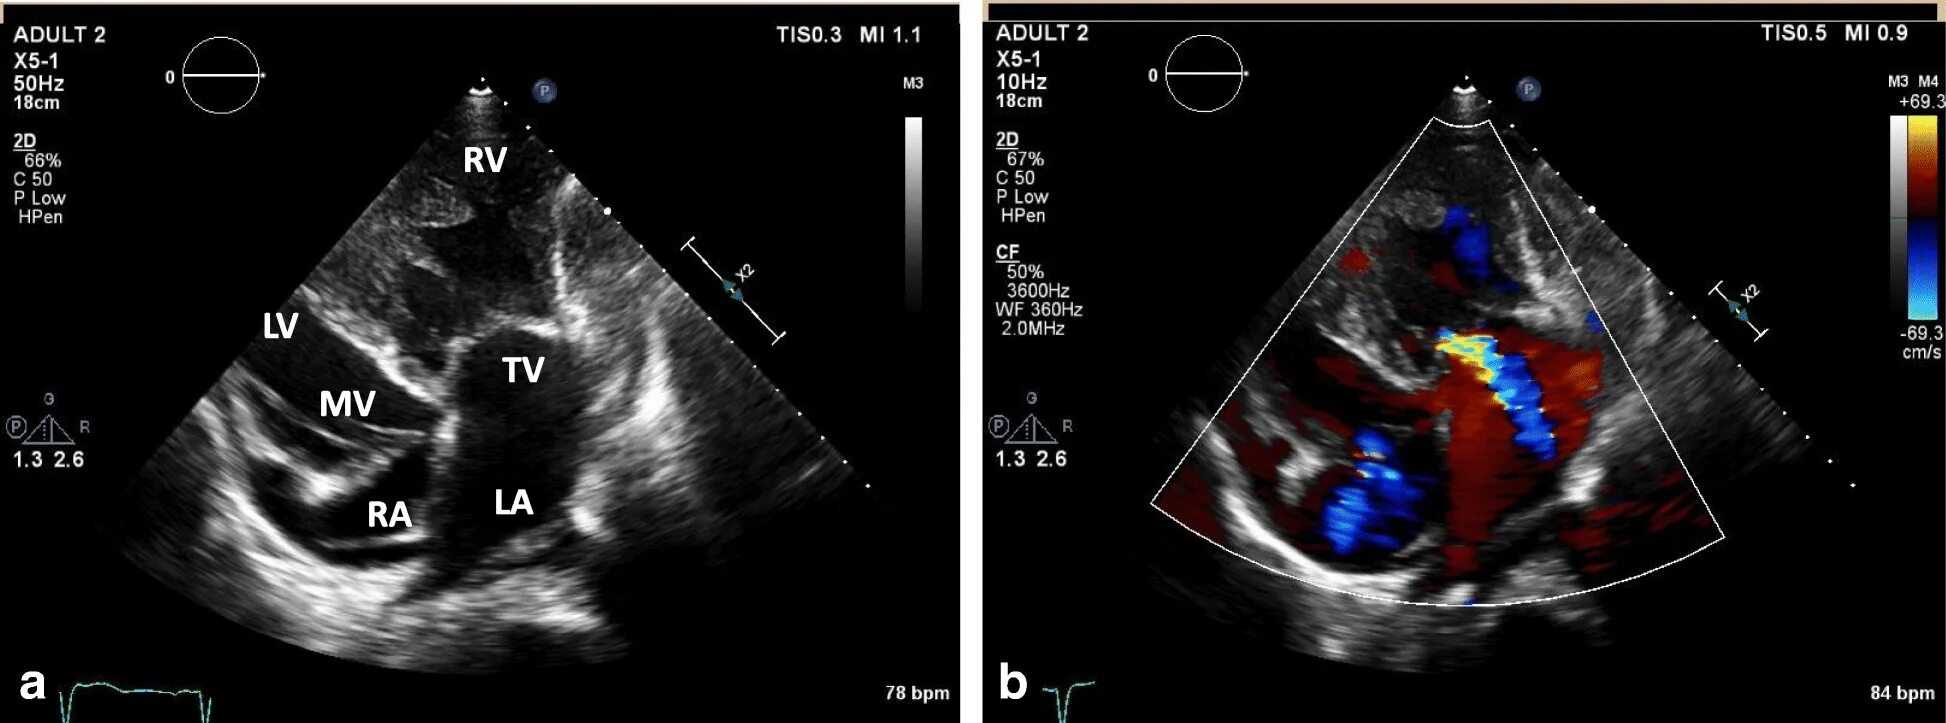

Аневризма мпп без